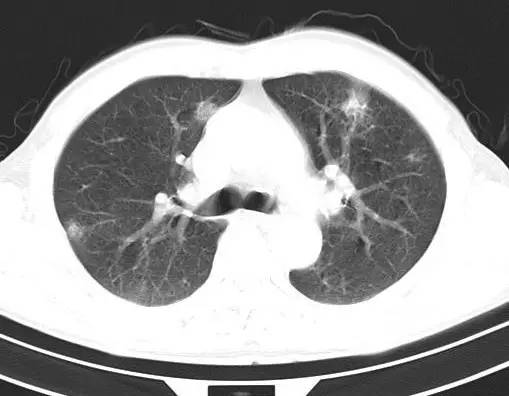

治疗前CT(图1-8):两肺胸膜下散在多发斑片状、结节状伴空洞影,边缘欠清晰。